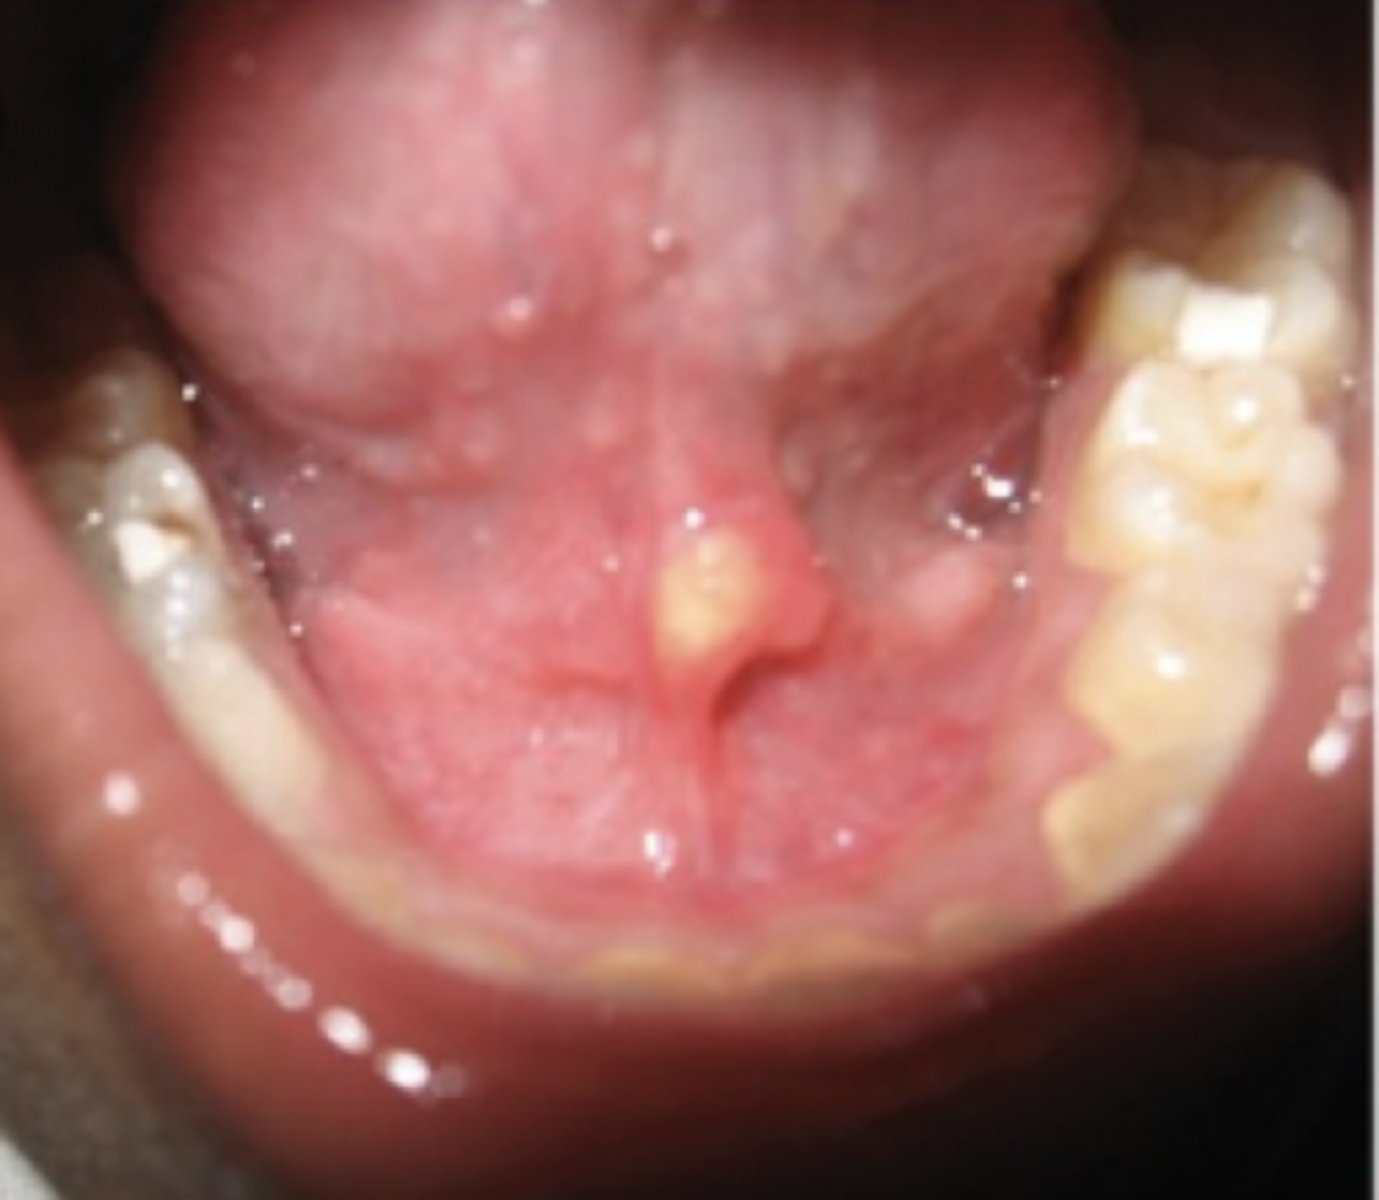

Necrotizing Sialometaplasia

Ischemia of the salivary glands of the hard palate, Often bilateral and symmetrical, starts out initially as a swelling

What condition can mimic squamous cell carcinoma?

Pseudoepitheliomatous hyperplasia, Coagulative necrosis of

the adjacent glands